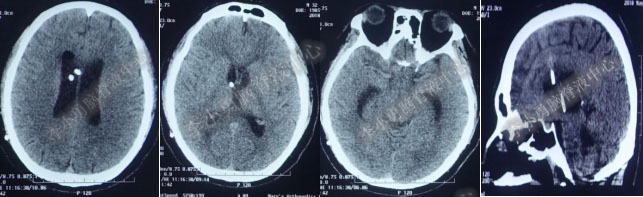

第3次软性内镜术后第6天即2018年4月24日复查头部CT(图-13)脑室系统仍扩张。

图-13:2018年4月24日头部CT

图-14:2018年5月4日头部CT

入院第22天即2018年5月6日(第3次软性内镜术后19天),患者意识昏睡,发热,复查头部CT(图-15)全脑室系统又扩大。

图-15:2018年5月6日复查头部CT

入院第38天即2018年 5月22日(第3次软性内镜术后35天),复查头部CT(图-16)显示侧脑室、四脑室仍扩张。

图-16:2018年 5月22日头部CT

入院时:慢性病态,体温高达38.9°C,昏睡,双侧眼球内聚,带脑室腹壁外引流管状态,脑脊液透明但色黄(图-17)。

图-17:2018年5月23日入院状态

图-18:2018年5月23日入院时头部CT

入院当天晚上因脑室腹壁引流管又第3次不通,意识昏迷,因此急诊床旁经原骨孔右侧脑室穿刺外引流术:右侧脑室具有两条引流管。术后当天复查头部CT(图-19)示脑室系统略有扩张。

图-19:2018年5月23日术后复查头部CT

图-20:2018年5月24日术后头部CT

图-21:2018年5月25日头部CT

图-22:2018年5月26日头部CT